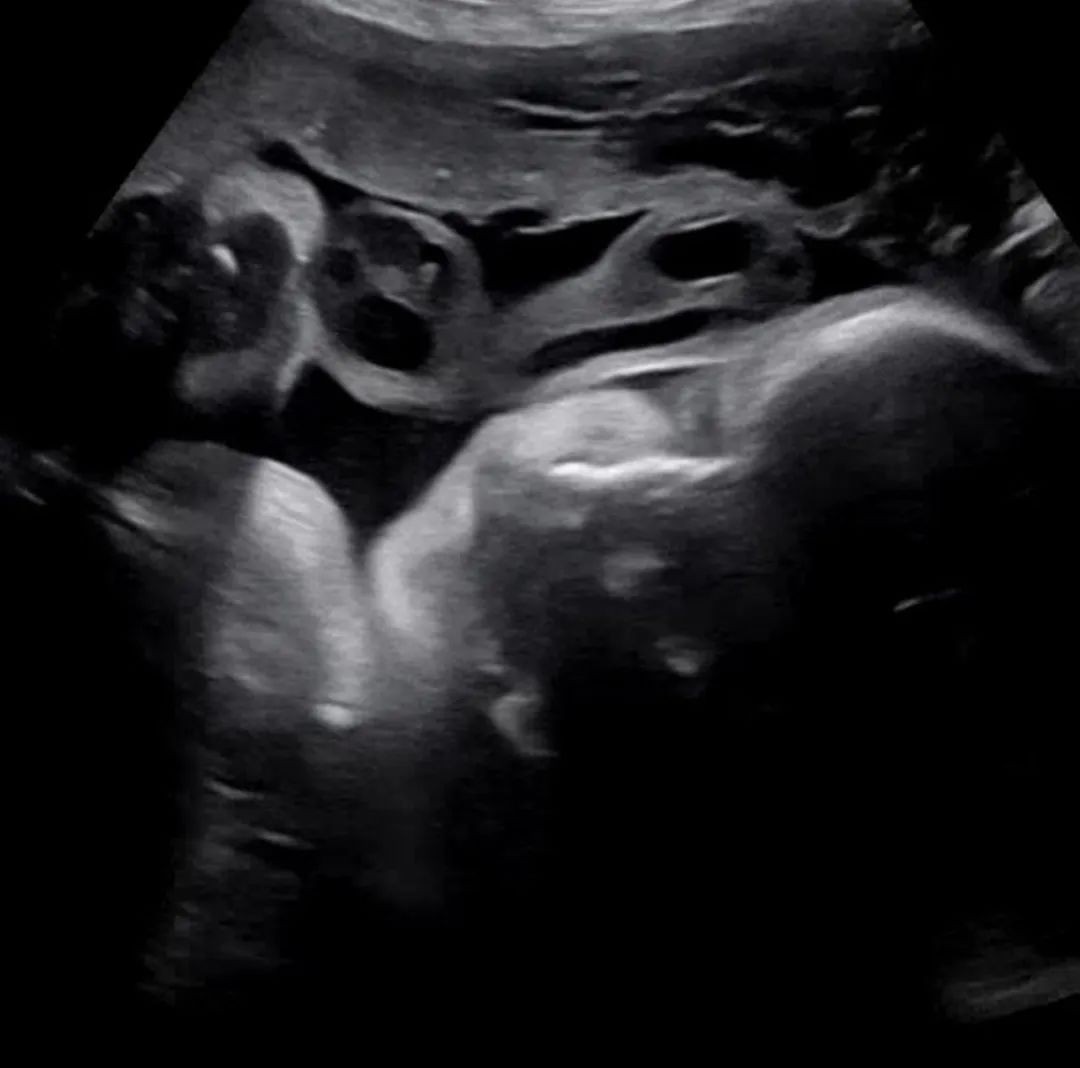

8月19日陈泰贤通过个人ins发表长文向网友及粉丝们告知:在离出生还有20天,8月16日妻子进行产检的当天,小baby的心脏无缘无故停止了跳动。

对此他也表达了自己遗憾的心情:原本再坚持三周(准确来说20天)就能见到孩子可爱的脸庞,9个月期间给爸爸妈妈带来希望和幸福,然而都没有见一面就离开了。因为收到了很多人的支持和鼓励,我们的baby真的很幸福来着。不过我们还是不后悔,会把这段时光当作回忆珍藏在心中。另外陈泰贤还表示自己会好好关爱妻子,竭尽全力帮助妻子身心上的恢复。

而且陈泰贤还将ins头像改为了胎儿B超的黑白照,同时个性签名中的“死产”一词也非常引人注目,可以感受到他的内心十分难受。